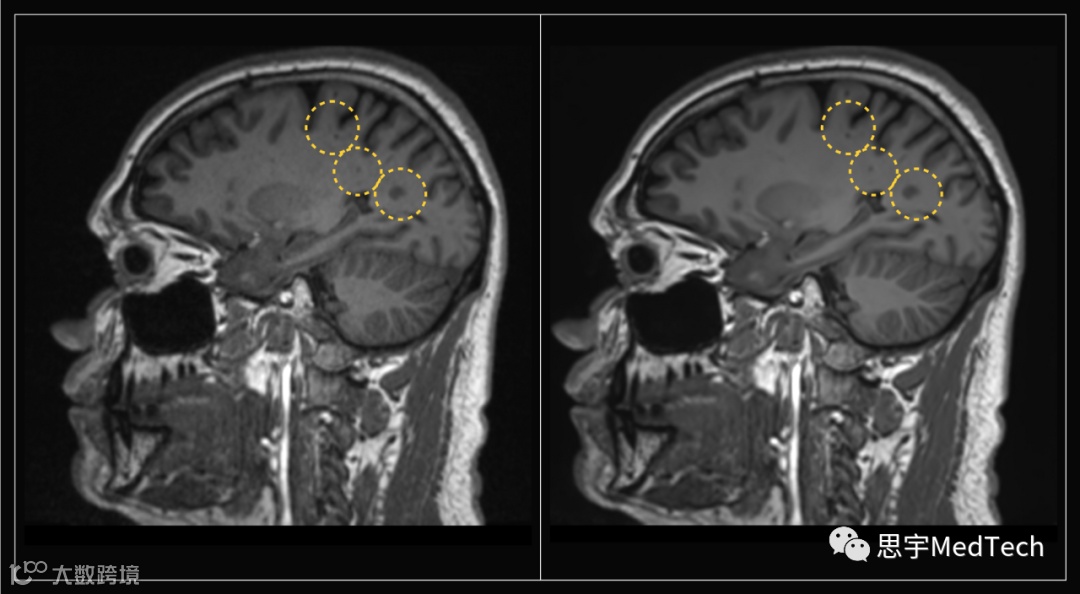

▲(图左为未使用AI技术形成的MRI图像,图右为Ezra Flash AI增强后图像)

该公司使用了多步验证过程,其中五名放射科医生对AI的性能进行了定性和定量分析。